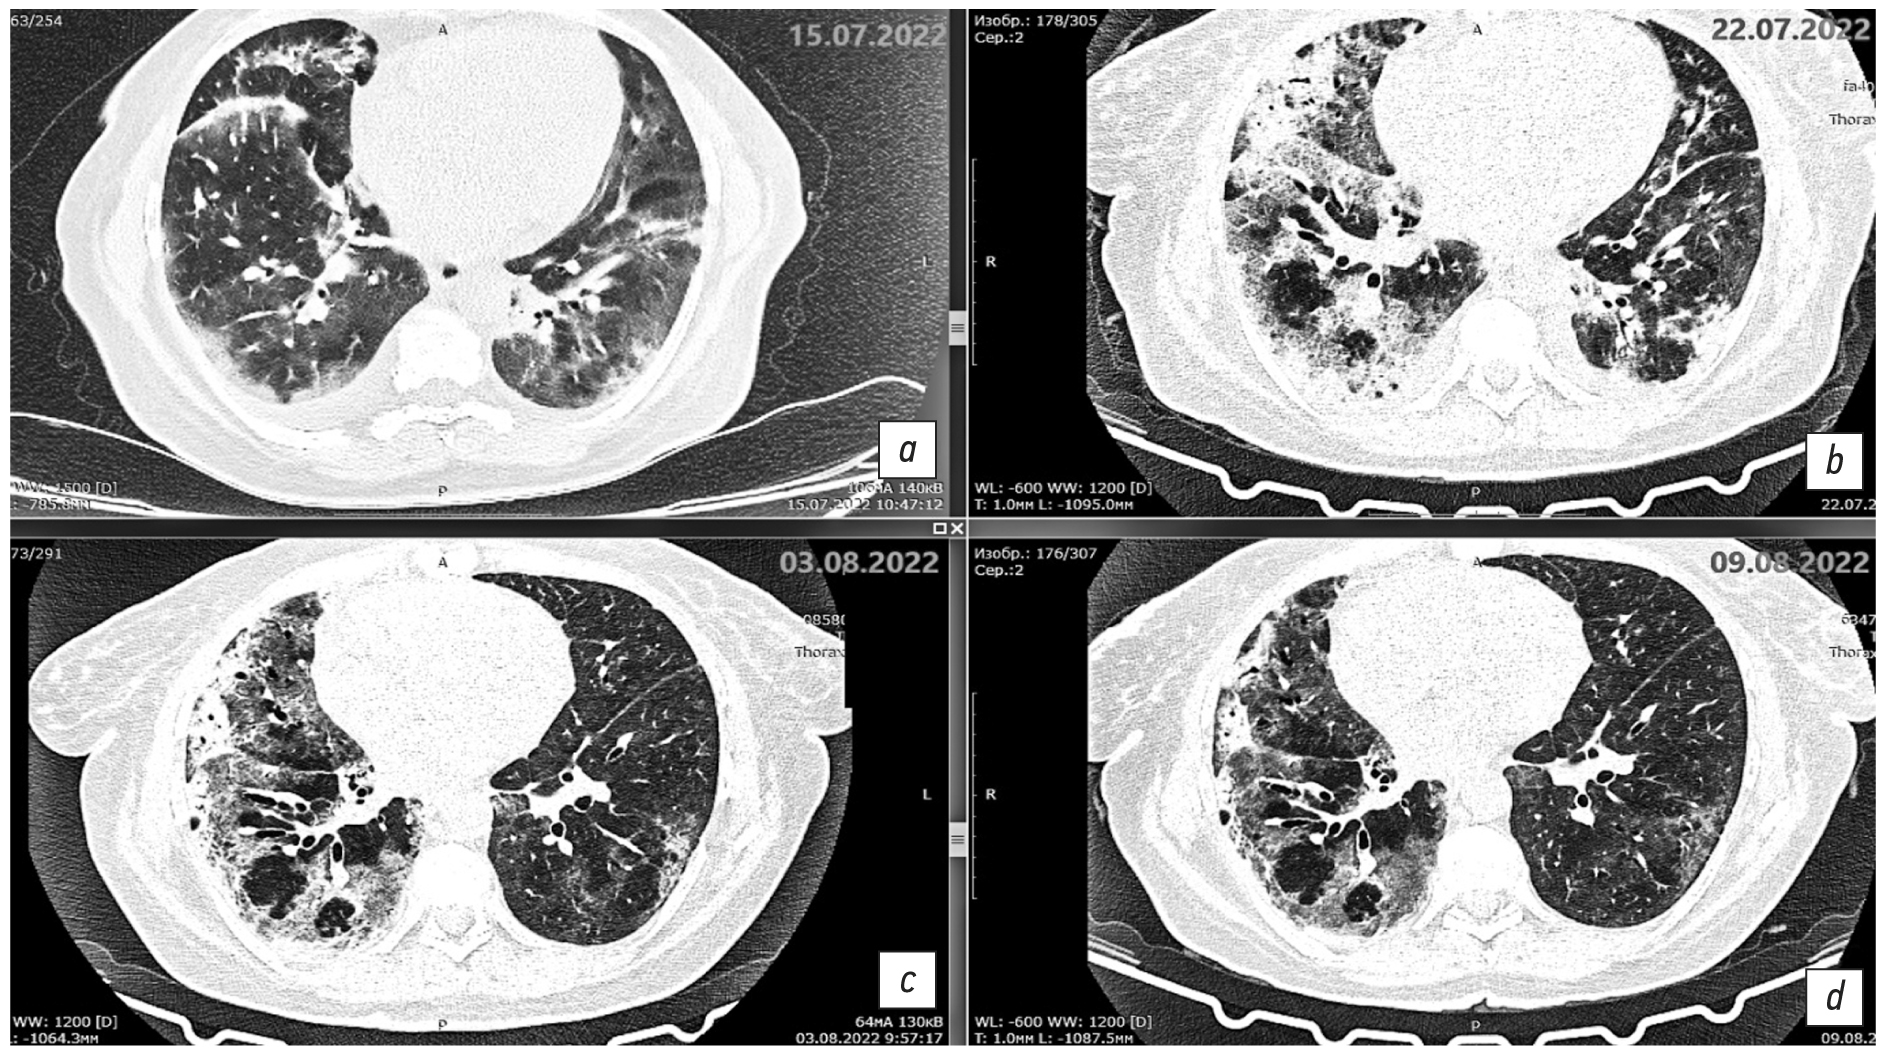

Fig. 2. Axial sections at the level of the main bronchi, pulmonary window. Changes in the areas of heterogeneous infiltration: a: chest CT scan dated July 15, 2022, day 11 of the disease, day 1 of hospitalization; b: chest CT scan dated July 22, 2022, day 18 of the disease, day 7 of hospitalization; c: chest CT scan dated August 3, 2022, day 30 of the disease, day 19 of hospitalization; d: chest CT scan dated August 9, 2022, day 36 of the disease, day 25 of hospitalization.

Fig. 3. Axial sections at the level of the basal parts of the lungs, pulmonary window. Changes in the areas of heterogeneous infiltration. a: chest CT scan dated July 15, 2022, day 11 of the disease, day 1 of hospitalization; b: chest CT scan dated July 22, 2022, day 18 of the disease, day 7 of hospitalization; c: chest CT scan dated August 3, 2022, day 30 of the disease, day 19 of hospitalization; d: chest CT scan dated August 9, 2022, day 36 of the disease, day 25 of hospitalization.

Description of the chest CT scan dated July 15, 2022 (Fig. 1a, 2a, 3a): The lungs are fully expanded. Pneumatization is diffusely reduced. The pulmonary pattern is deformed. Both lungs show multifocal infiltrative changes of the pulmonary parenchyma of a ground-glass type with reticular shadows and peribronchial consolidation type. The infiltrative changes are located randomly. The parenchyma is visibly involved. Up to 30% and 60% of the pulmonary parenchyma is affected in the left upper and lower lobes, respectively. Up to 60% of the pulmonary parenchyma is affected in the right upper and lower lobes. The volume of the affected parenchyma in the left lung is up to 45% and less than 70% in the right lung. The total percentage of lung damage reaches 70%. The degree of severity is at the CT3 level.

The configuration and lumen of the trunk bronchi are unremarkable. The mediastinum is of normal shape and location. A layer of free fluid, up to 20 mm in thickness, is observed in the upper aortic pouch. The intrathoracic lymph nodes are indurated and enlarged. The para-aortic group is 11 mm along the short axis, the paratracheal group is up to 12 mm, the bifurcation group is up to 17 mm, and both bronchopulmonary groups are up to 12 mm. The major vessels are of normal structural organization and sizes. In both pleural cavities, a layer of free fluid is observed, measuring up to 15 mm along the posterior wall on the right side and up to 5 mm on the left side. Results: Bilateral multifocal pneumonia, intermediate probability of COVID-19 pneumonia (pneumonia of other etiology?), CT3, 65%–70%. Enlarged mediastinal lymph nodes, hydropericardium, bilateral hydrothorax, and focal mass in the left breast.

On day 18 of the disease and day 7 of the hospital stay, the chest CT scan dated July 22, 2022 (Fig. 1b, 2b, 3b) revealed negative changes in bilateral multifocal pneumonia and weakly negative changes in bilateral pneumothorax and hydropericardium. Moderate intrathoracic lymphadenopathy without changes and a focal mass in the left breast were observed. Antibiotic therapy was re-adjusted; rifampicin was discontinued, and intravenous tigecycline 100 mg daily was added to levofloxacin 1 g daily. This regimen demonstrated gradual positive changes.

Since August 1, 2022 (day 28 of the disease, day 17 of inpatient treatment), the patient’s condition was of average severity, with normalized body temperature, decreased symptoms of respiratory insufficiency, and persistent weakness. The air saturation was 89% and 97% with humidified insufflation at 4 L/min. The chest CT scan dated August 3, 2022 revealed mixed changes of bilateral multifocal pneumonia. The left lung exhibited positive findings, whereas the right lung displayed cavitary lesions. The presence of a dilated bronchial lumen and heterogeneous infiltration were suspected. The regression of bilateral hydrothorax was accompanied by negative changes in hydropericardium.

Description of the chest CT scan dated August 3, 2022 (Fig. 1c, 2c, 3c): The lung volume increased due to regression of fluid in the pleural cavities on both sides. Previously, the maximum fluid level was 21 mm on the right side and up to 19 mm on the left side, with a flow along the interlobular pleura up to 17 mm. Multiple segments of the lungs exhibit extensive confluent areas of heterogeneous infiltration, predominantly of the consolidation type. Within these areas, the lumen of dilated bronchi and a ground glass appearance is observed, accompanied by a single discoid atelectasis. The changes have no preferred localization. A marked continuous reduction in the extent and intensity of changes in the left lung is observed, with preserved ground-glass changes and consolidation (S1/2).

The extent of changes in the right lung remains unaltered. However, an increase in consolidation is observed in the upper regions. Additionally, heterogeneous infiltration in the right lung in S6 and S10 segments caused cavitary lesions up to 9 × 7 mm and 4 × 5 mm, respectively. This phenomenon is likely attributable to the dilation of the bronchial lumen, heterogeneous expansion of infiltration, or the formation of a destruction cavity.

On August 10, 2022 (day 37 of the disease, day 26 of hospitalization), the patient’s condition was deemed satisfactory. The patient reported a rare dry cough and slight exertional dyspnea. The patient’s air saturation was 97%. The chest CT scan dated August 9, 2022 (Fig. 1d, 2d, 3d) demonstrated positive changes in bilateral multifocal pneumonia, with a decrease in intensity. Additionally, there were no changes in cavitary lesions in the right lung, which could be attributed to dilated bronchial lumen or heterogeneous infiltration. Hydropericardium also showed positive changes.